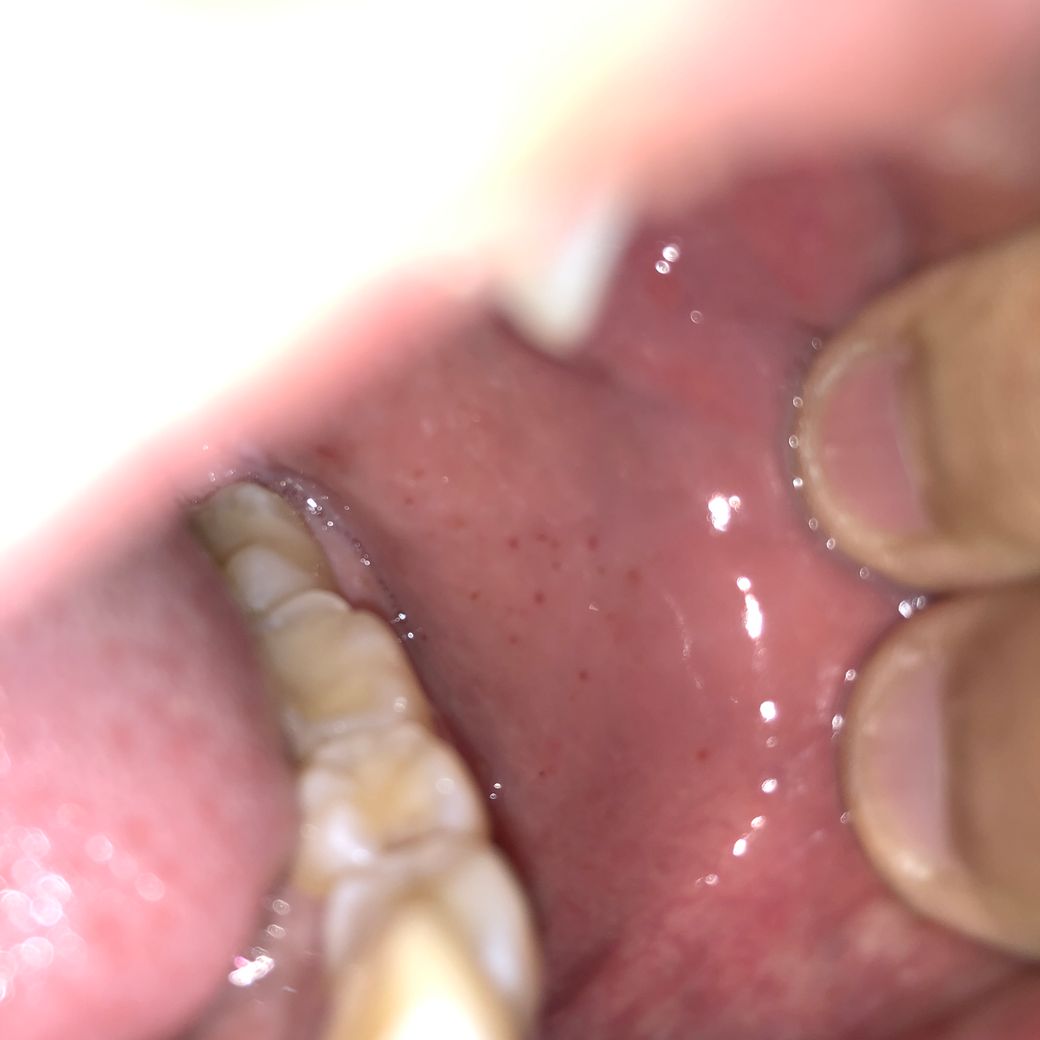

볼안 점막에 양쪽에 이런 점상출혈이 생겼다 없어졌다하는데 이번주는 좀 많이 생겼습니다.

• 1번 째 사진

안타깝게도 구강 점막의 점살 출혈을 유발할 수 있는 원인은 외상부터 시작하여 혈소판 이상, 응고인자결핍, 혈관의 문제 등등 굉장히 다양하며 증상만 가지고는 원인을 찾기가 매우 어렵습니다. 진료 및 정밀 검사를 통해서 정확한 진단을 받으실 필요가 있어 보입니다.

포다이스반등의 질환이 의심됩니다. 경과관찰 하시다가 병원 방문일에 맞춰 치과치료도 병행해보시기 바랍니다.

현재 점상출혈이 구강내에 생긴 것으로 보이며 점상 출혈은 외상이나 혈소판이나 혈액응고인자의 문제가 있을 경우에도 자발적으로 발생할 수 있어 현재로서는 명확한 원인을 확인하기는 어렵습니다. 내원하시어 기본적인 진료 및 혈액검사를 받아보시는 것이 좋겠습니다.